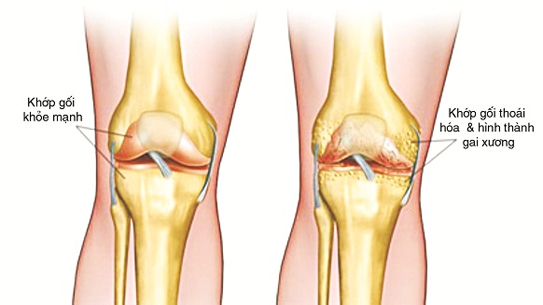

Triệu chứng thoái hóa khớp

Thông thường thoái hóa khớp có diễn biến khá chậm. Ở giai đoạn sớm, khớp thường bị đau sau khi vận động. Dần dần bệnh nhân sẽ cảm thấy cứng khớp, đặc biệt là sau khi ngủ dậy vào buổi sáng hoặc sau khi giữ nguyên một tư thế trong một thời gian nhất định. Thoái hóa khớp thường xuất hiện ở khớp gối, khớp bàn tay, khớp háng, cột sống.